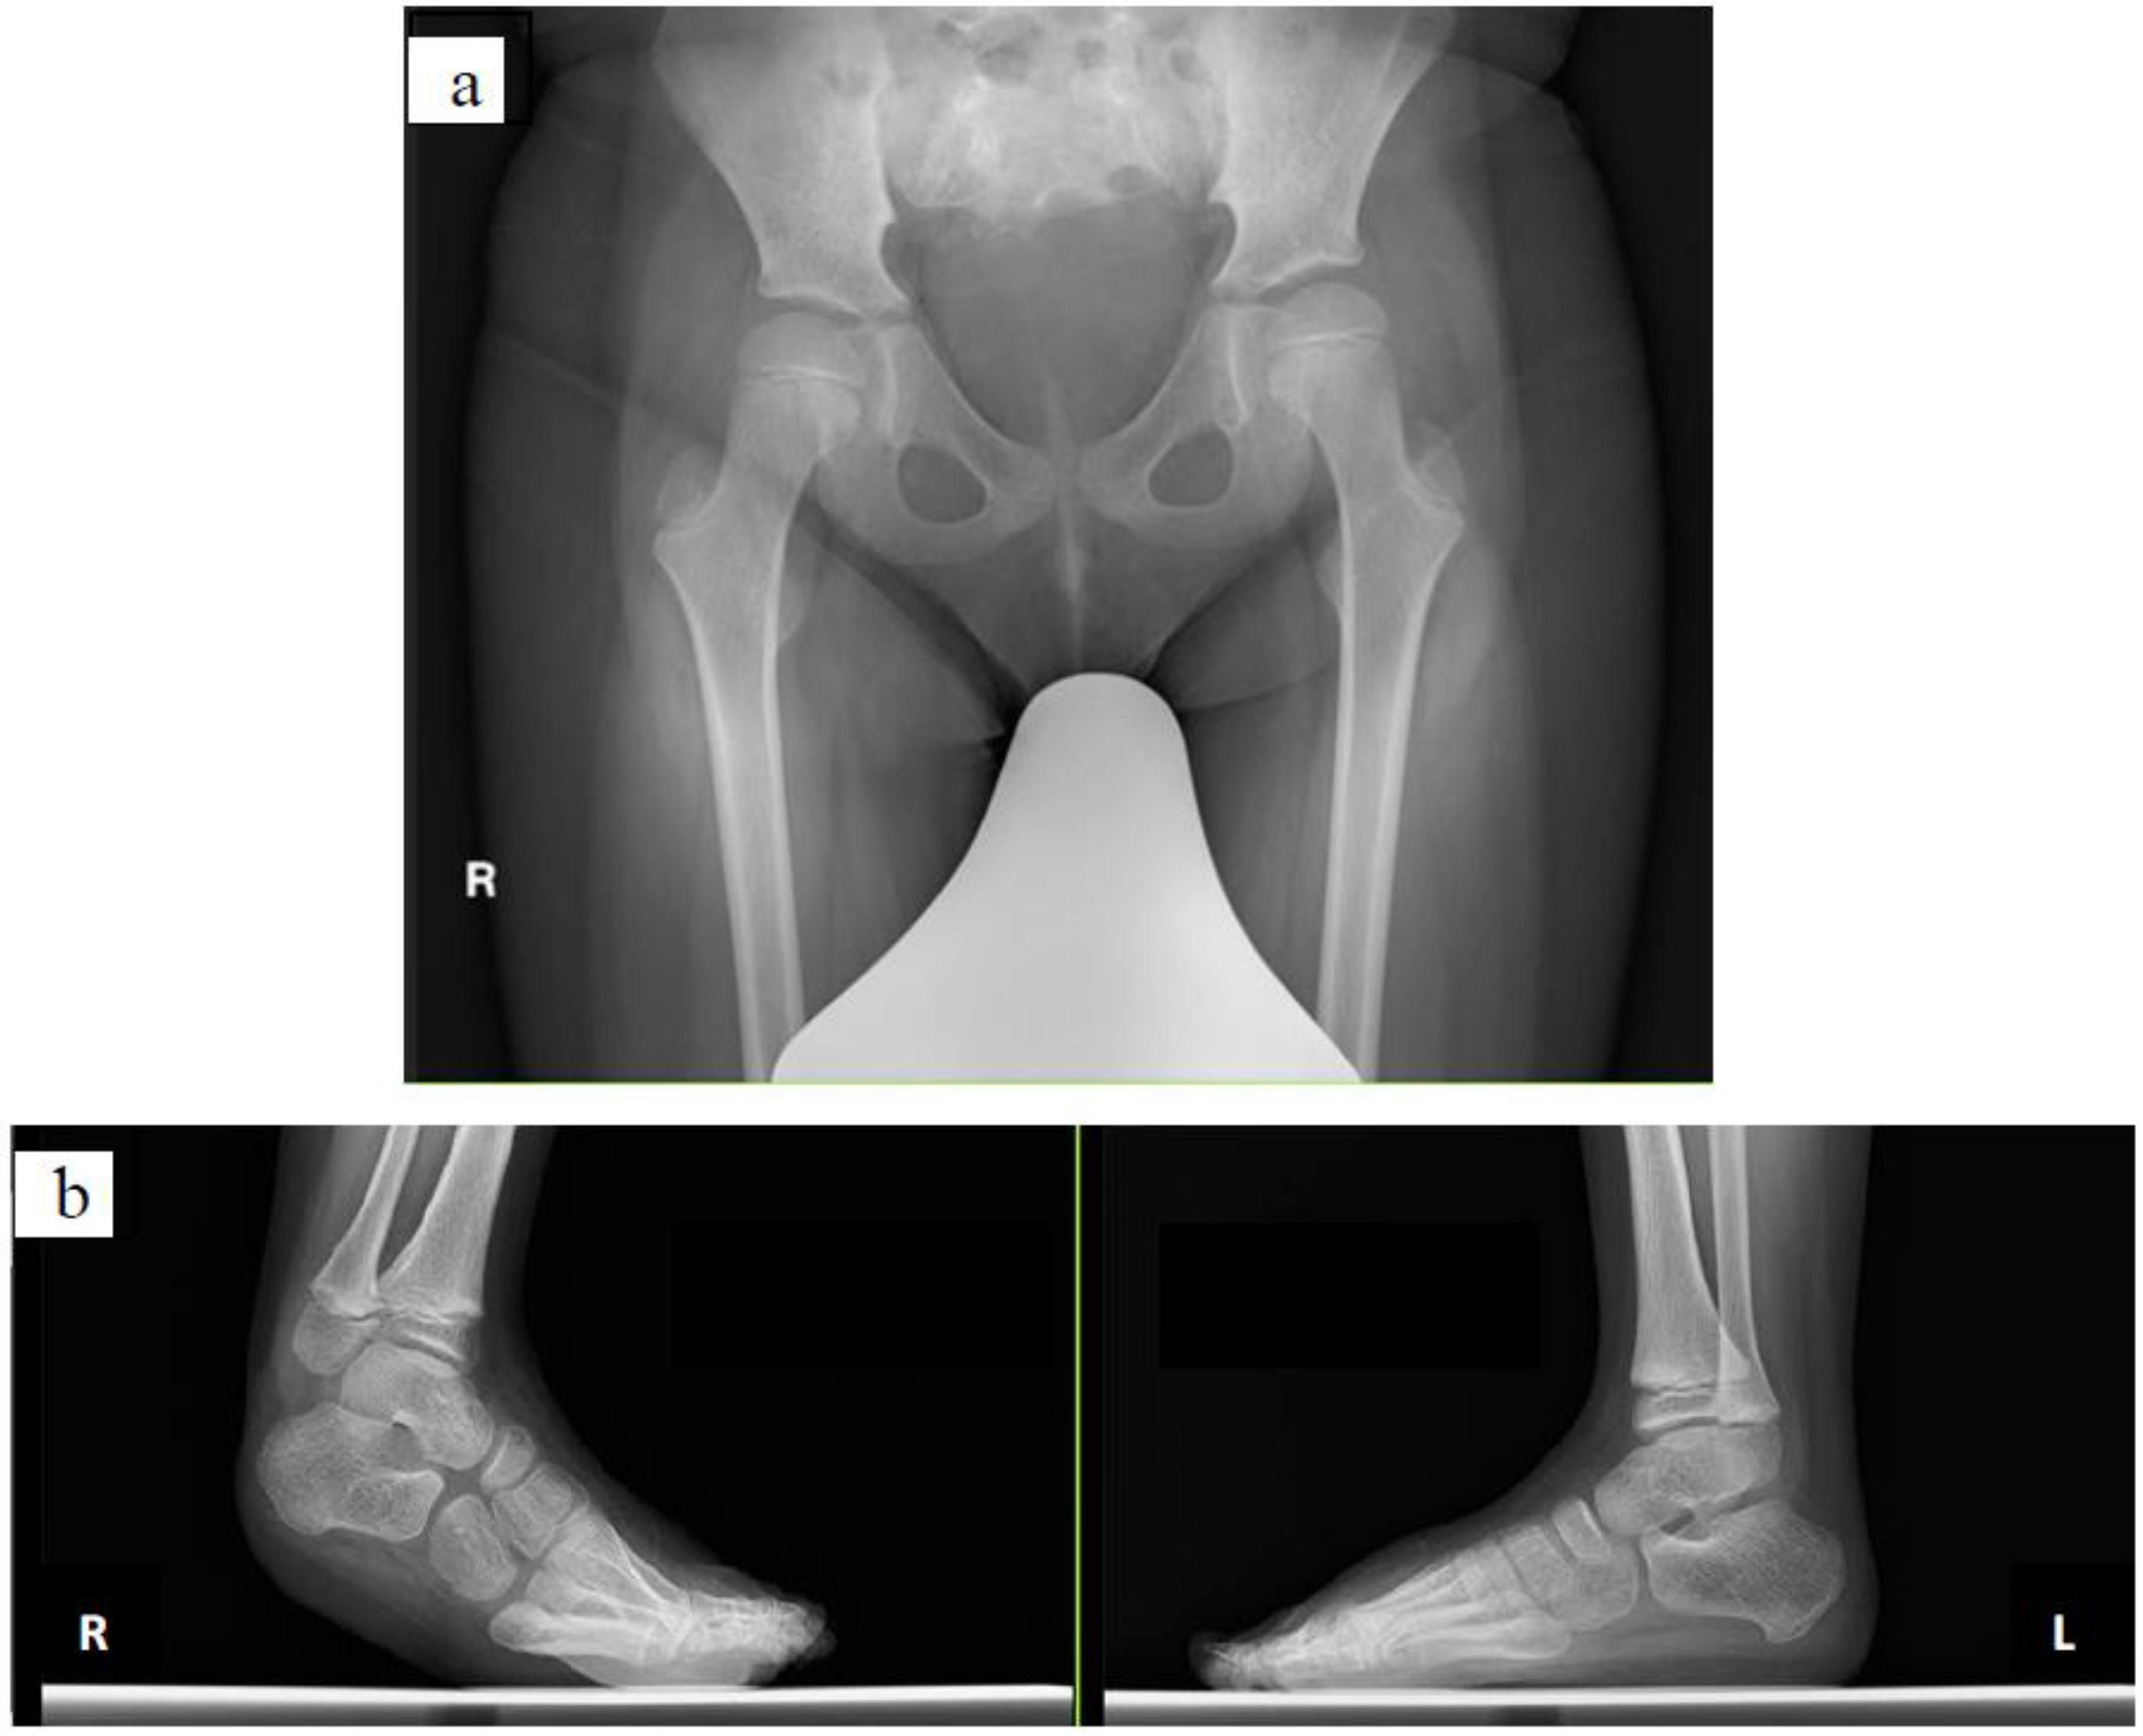

2.2.1. Case 1

2.2.2. Case 2